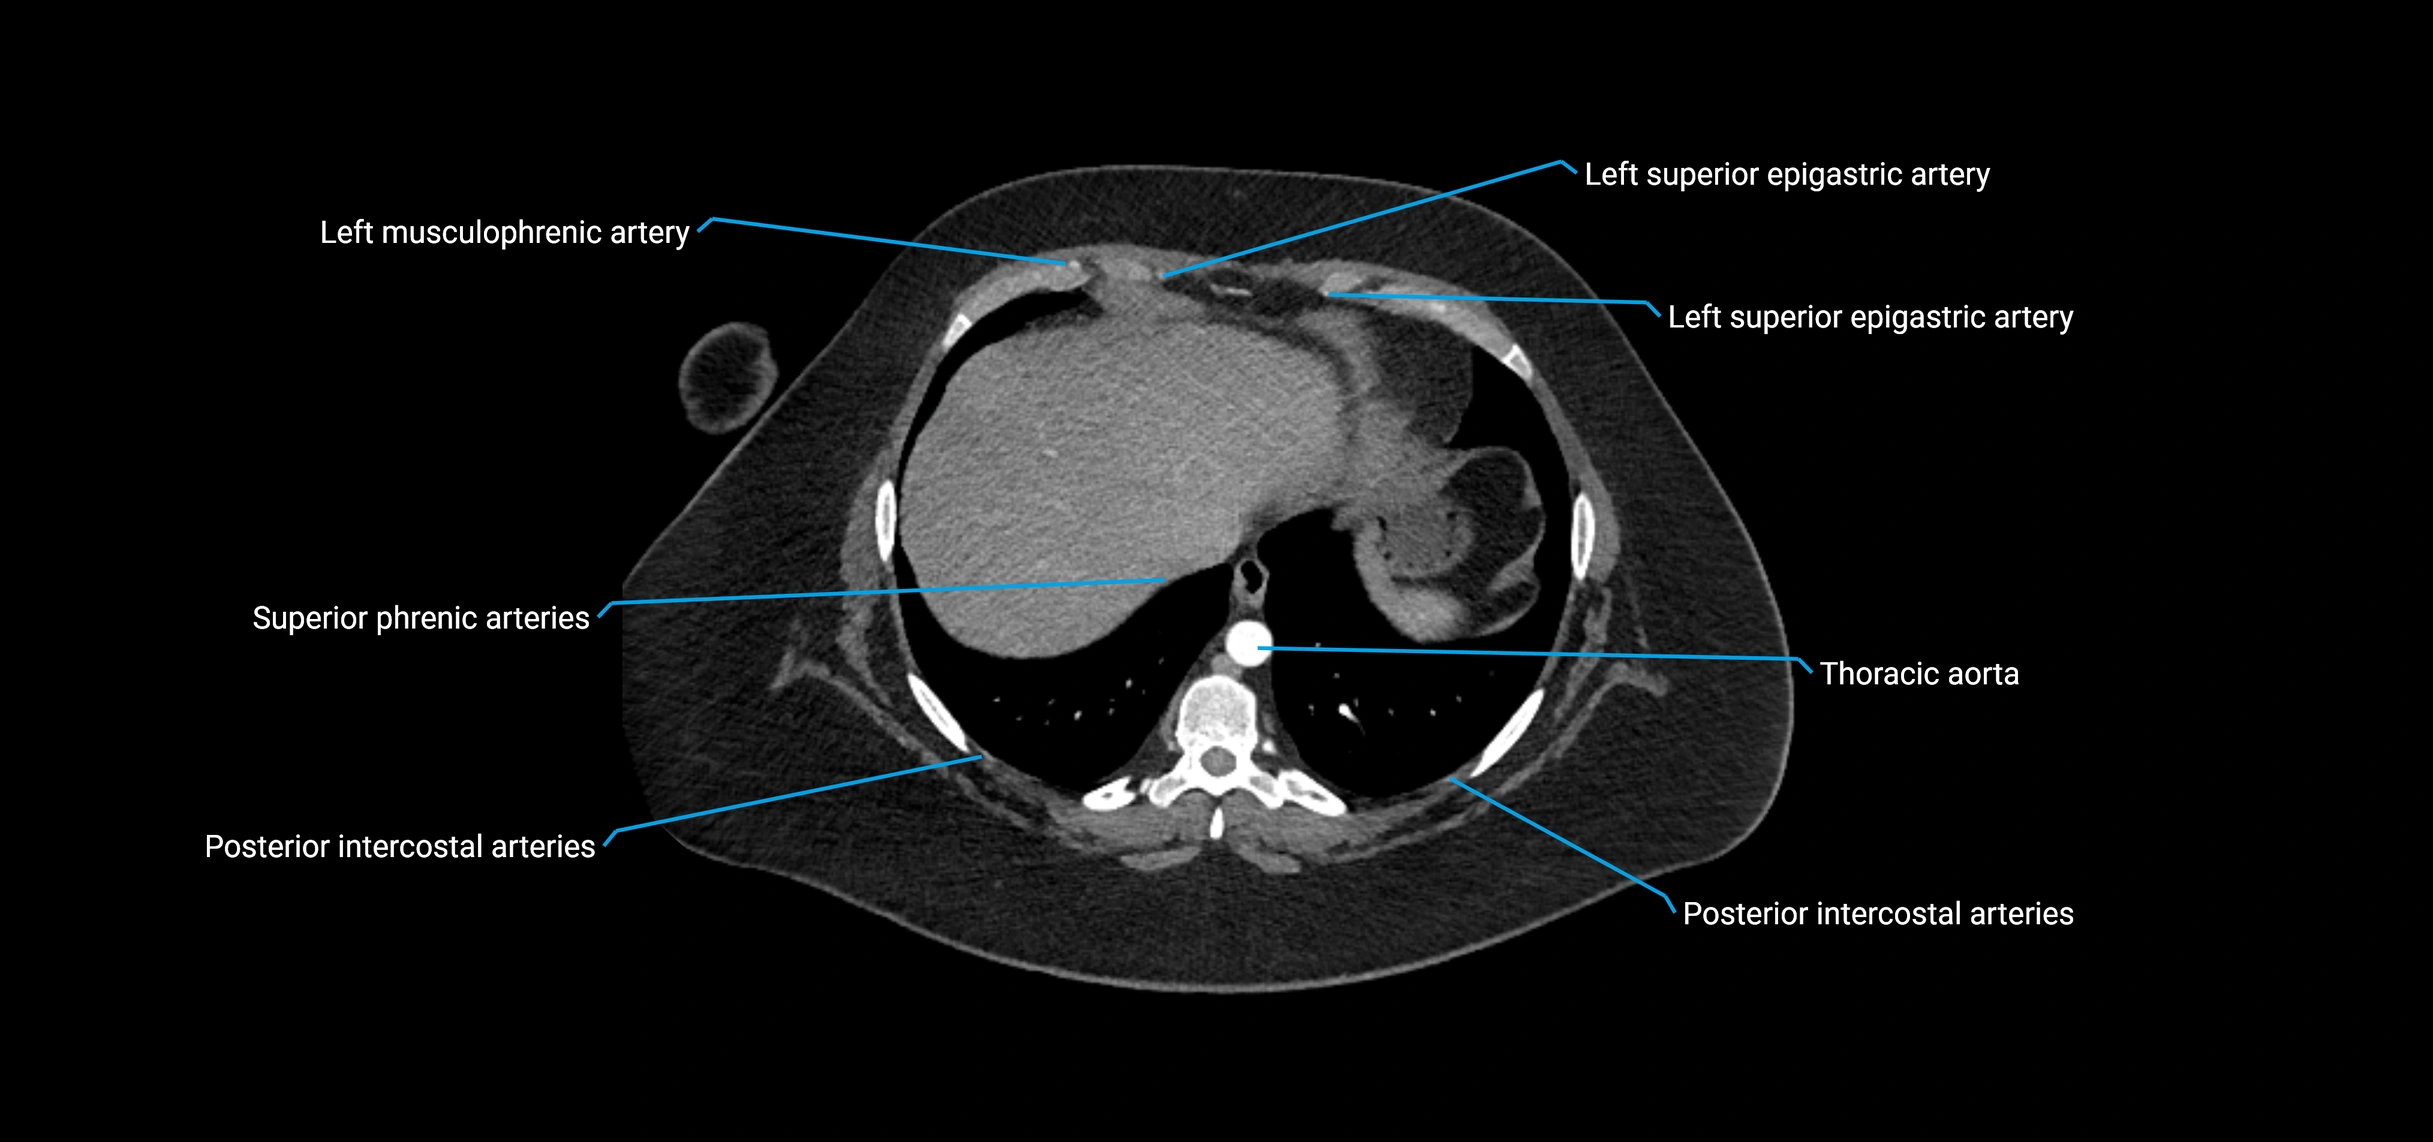

CT Appearance

Non-contrast CT:

• Appears as a tubular soft tissue structure anterior to vertebral bodies

• Calcified atherosclerotic plaques appear as hyperdense foci along the wall

• Useful for screening abdominal aortic aneurysm (AAA) size and mural calcification

Contrast-enhanced CT (CTA):

• Gold standard for abdominal aortic imaging

• Provides excellent detail of lumen, wall, aneurysm, thrombus, and branch vessels

• Multiplanar and 3D reconstructions help in aneurysm measurement, stent graft planning, and dissection evaluation

• Detects acute rupture, traumatic injury, or occlusion with high sensitivity

CT images

image